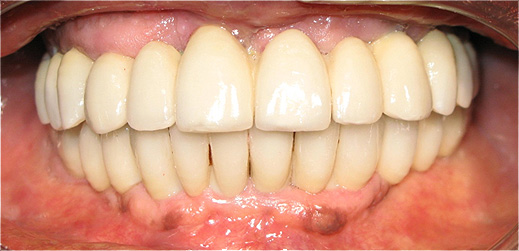

Resultado de colocação de implante dentário na Clínica São Filinto

Caso 8 - Colocação de implantes dentários para reabilitação com prótese fixa em zircónio cerâmica no 4º quadrante.

![]() |